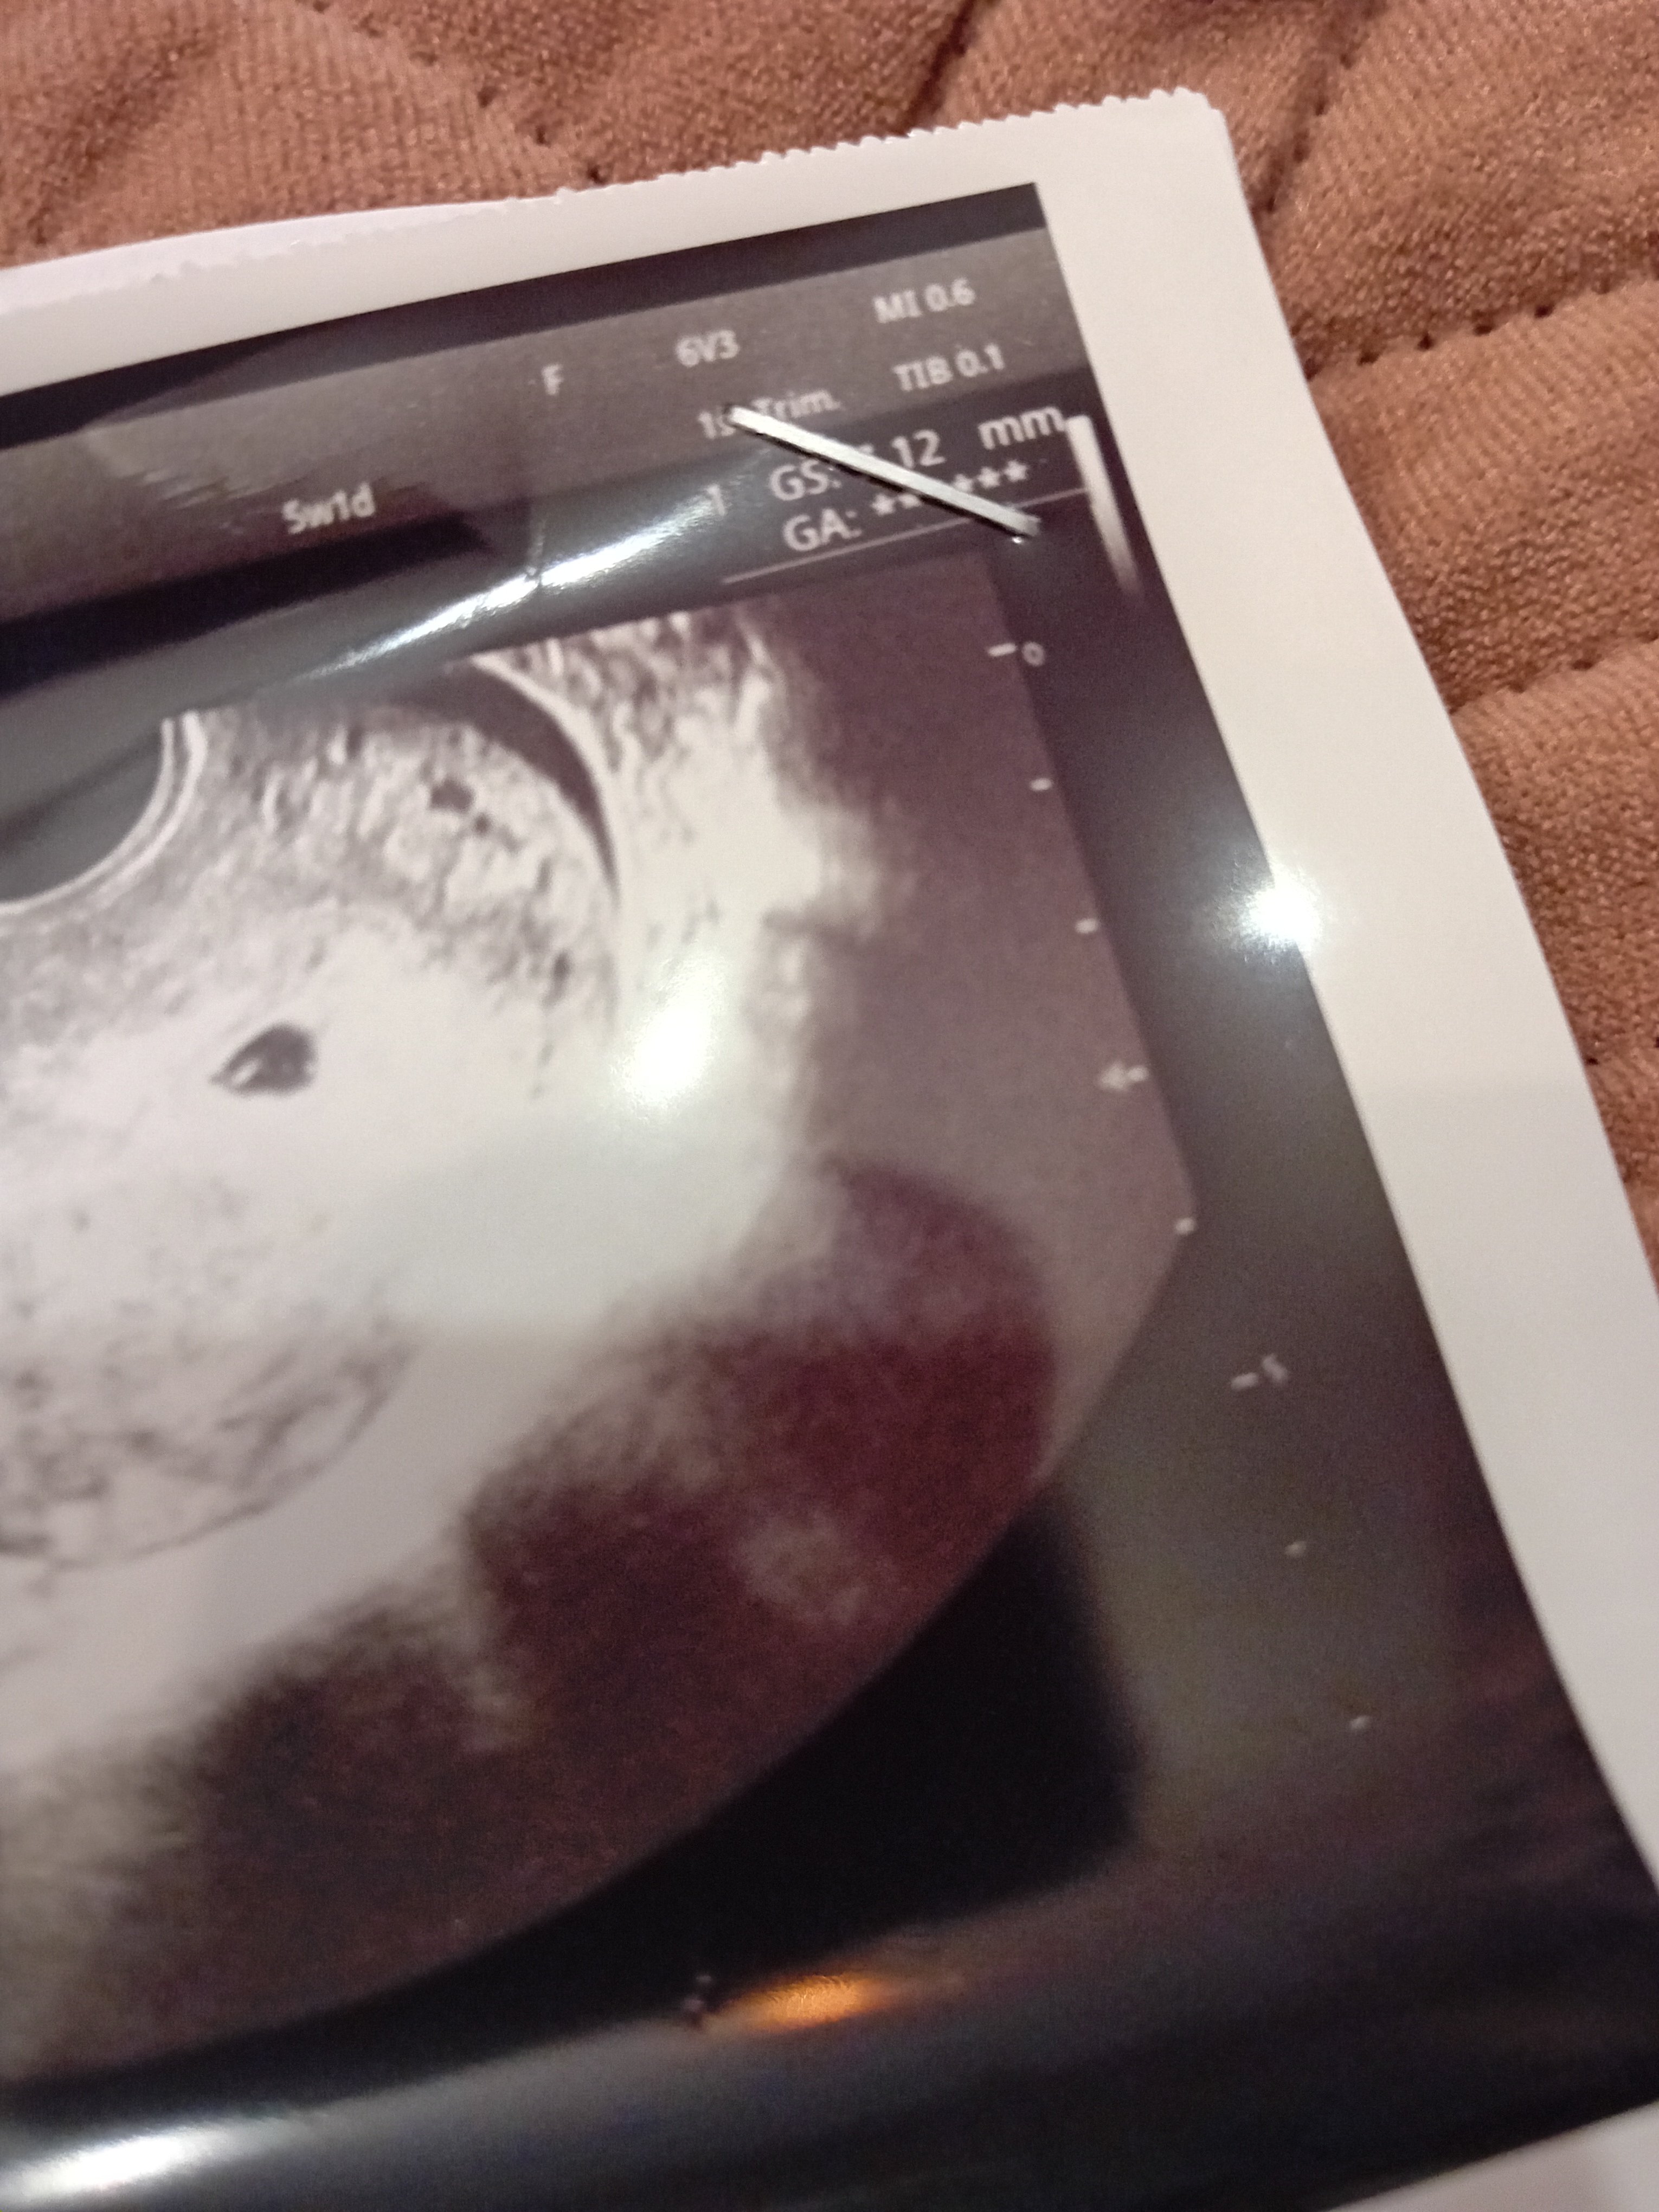

Dzisiaj 5+1, gin uspokajała, że często nawet pęcherzyka ciążowego nie widać, a tu dzisiaj pęcherzyk żółtkowy nawet 😍😍

Wrzucam zdjęcie kropki 😅 kolejną wizyta dopiero 7.01

Ja też jestem 5+1 dzisiaj, ale miałam wcześniej owu. Pik w 13dc. Wrzuciłam usg z dzis

Myślę, że wszystko ok u ciebie 😊😊😊